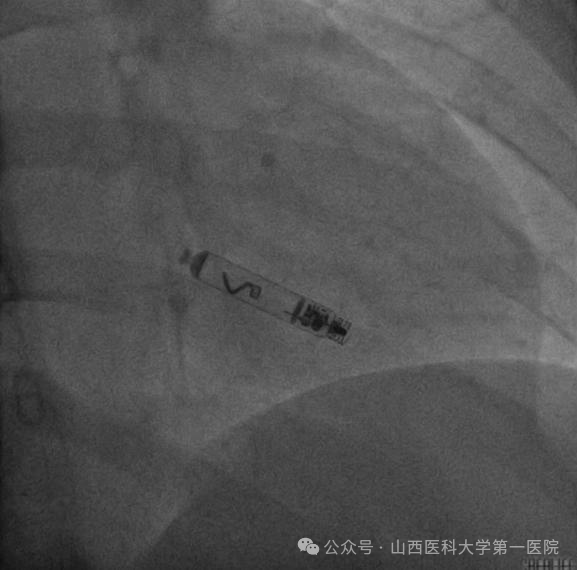

心血管内科与烧伤整形外科联合会诊后,认为心脏起搏器囊袋感染是少见而疑难的起搏器术后并发症,该患者为疤痕体质,两次起搏器术后均出现疤痕挛缩,起搏器外移导致起搏器囊袋破溃、感染,且感染一旦扩散,就可能导致感染性心内膜炎、脓毒血症,甚至危及生命,目前最佳的处理方式只有完全拔除原有起搏器系统。此治疗存在两个难点,第一,患者起搏器植入已经2年,可能存在电极与心肌组织黏连严重,拔除存在一定风险;第二,如采用常规对侧植入起搏器的方法有可能再次出现瘢痕挛缩、破溃情况,会给患者身体健康、家庭经济以及思想上造成极大负担。电生理团队与张女士沟通后考虑植入目前国际上首款可移除式主动螺旋式无导线起搏器替换原有起搏器。

2024年11月患者再次住院手术,在心外科团队保驾护航下,心血管内科电生理团队经过3个小时的努力,成功拔除原双腔起搏器电极,进行囊袋清创后成功植入无导线起搏器。两天后,患者转至烧伤整形外科进行囊袋美容缝合,一周后顺利出院。出院后,张女士伤口愈合良好,亦无需术肢制动,一扫往日阴霾的她终于恢复了笑容:“囊带反复感染使我身心备受折磨,现在终于自由了,非常感谢心血管内科电生理团队。”

王睿主任医师表示,近年来心脏电子植入装置的使用越来越多,临床上不免能遇到起搏器囊袋感染的患者,对于囊带反复感染、血管入路异常的患者无导线起搏器是一种较好选择,国际国内指南也推荐对于此类患者植入无导线起搏器。无导线起搏器是将导线和脉冲发生器合二为一,比传统心脏起搏器减小93%,类似平常服用的胶囊大小,可以直接置于心腔内起到起搏心脏的作用。无导线起搏器植入无需外科切口、制作囊袋和置入电极导线,对于植入径路异常的患者、反复起搏系统感染及感染性心内膜炎的患者、一些起搏感染风险高的患者,比如长期使用激素或免疫抑制剂、反复感染、高龄、多种严重并发症、重度消瘦、严重皮肤疾病等,应该考虑植入无导线起搏器。